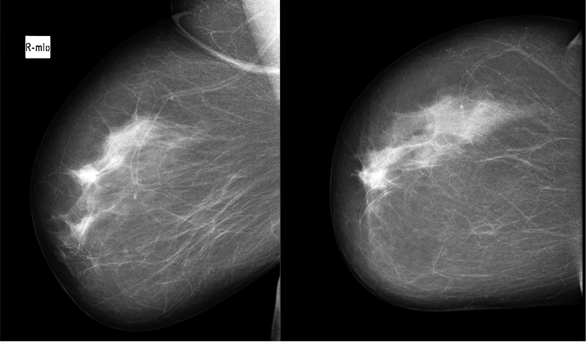

Fig. 2. Local hyperdense zone was seen in mammogram

During physical examination a 2 cm hard, not tender, with ill-defined margins lump in the upper inner quadrant of the right breast has been found. There was no nipple retraction, discharge or skin change. A breast ultrasound showed a 1.24x0.85 cm suspicious ill-defined hypoechogenic lesion at 1 o’clock position of the right breast (Figure 1). Mammogram revealed a local hyperdense zone in the right breast (Figure 2). Histopathological examination of the tumour core biopsy material revealed desmoid type fibromatosis. The patient underwent wide local with clear margins excision of the lesion. Histopathological examination of surgical material confirmed desmoid type fibromatosis (Figure 3). Tumour was poorly demarcated, composed of spindle-shape myofibroblasts arranged in long sweeping fascicles. There was no mitotic activity. Immunohistochemical findings of the mass showed a focally positive reaction with beta-catenin, and a negative reaction for CD34, Desmin, CK. The patient did not require any adjuvant treatment. There was no recurrence after two years of follow-up.

Mammographically breast desmoid tumour appears as a speculated mass [4, 8]. Moreover, rarely it may demonstrate calcified deposits [4]. Magnetic resonance imaging (MRI) is the best radiological diagnose method for diagnosing desmoid tumour [5]. On MRI images desmoid tumour may look as ill-defined hypointense or isointese masses on T1-weighted images or hyperintense masses on T2-weighted images [2].